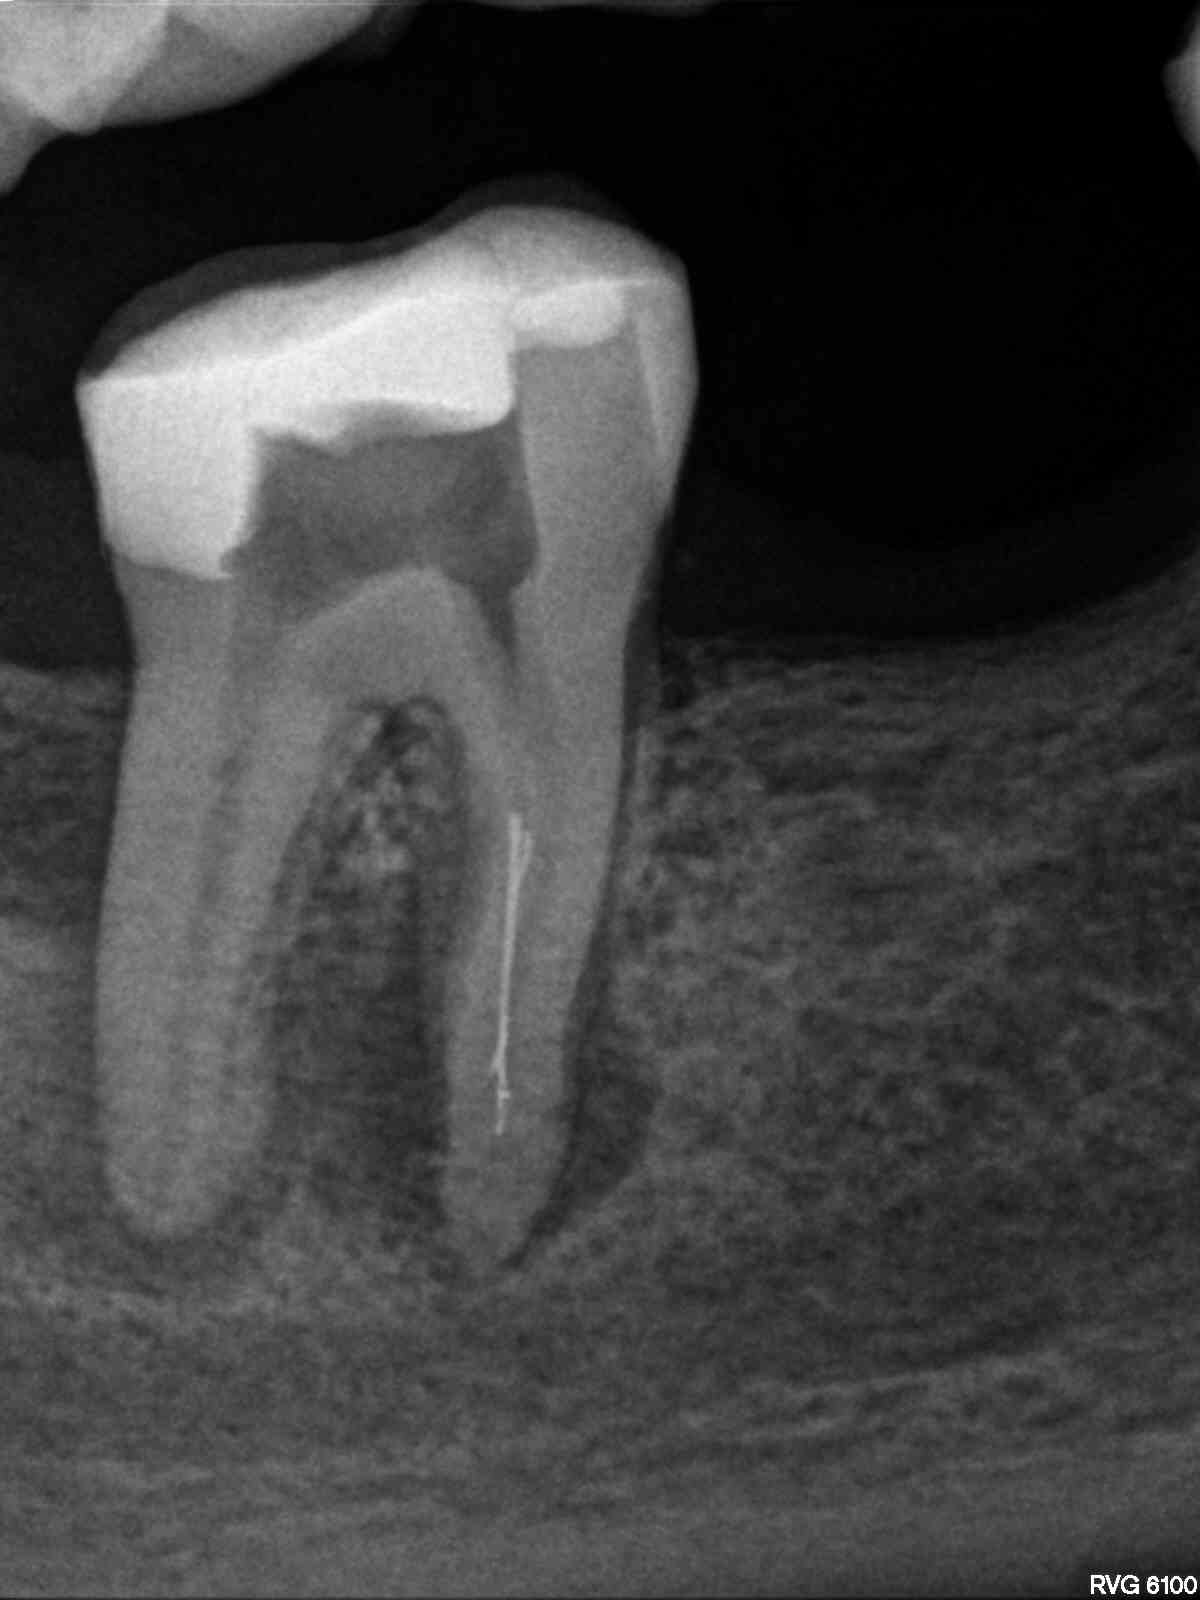

R1

1200 × 1600

8 auf einen Streich